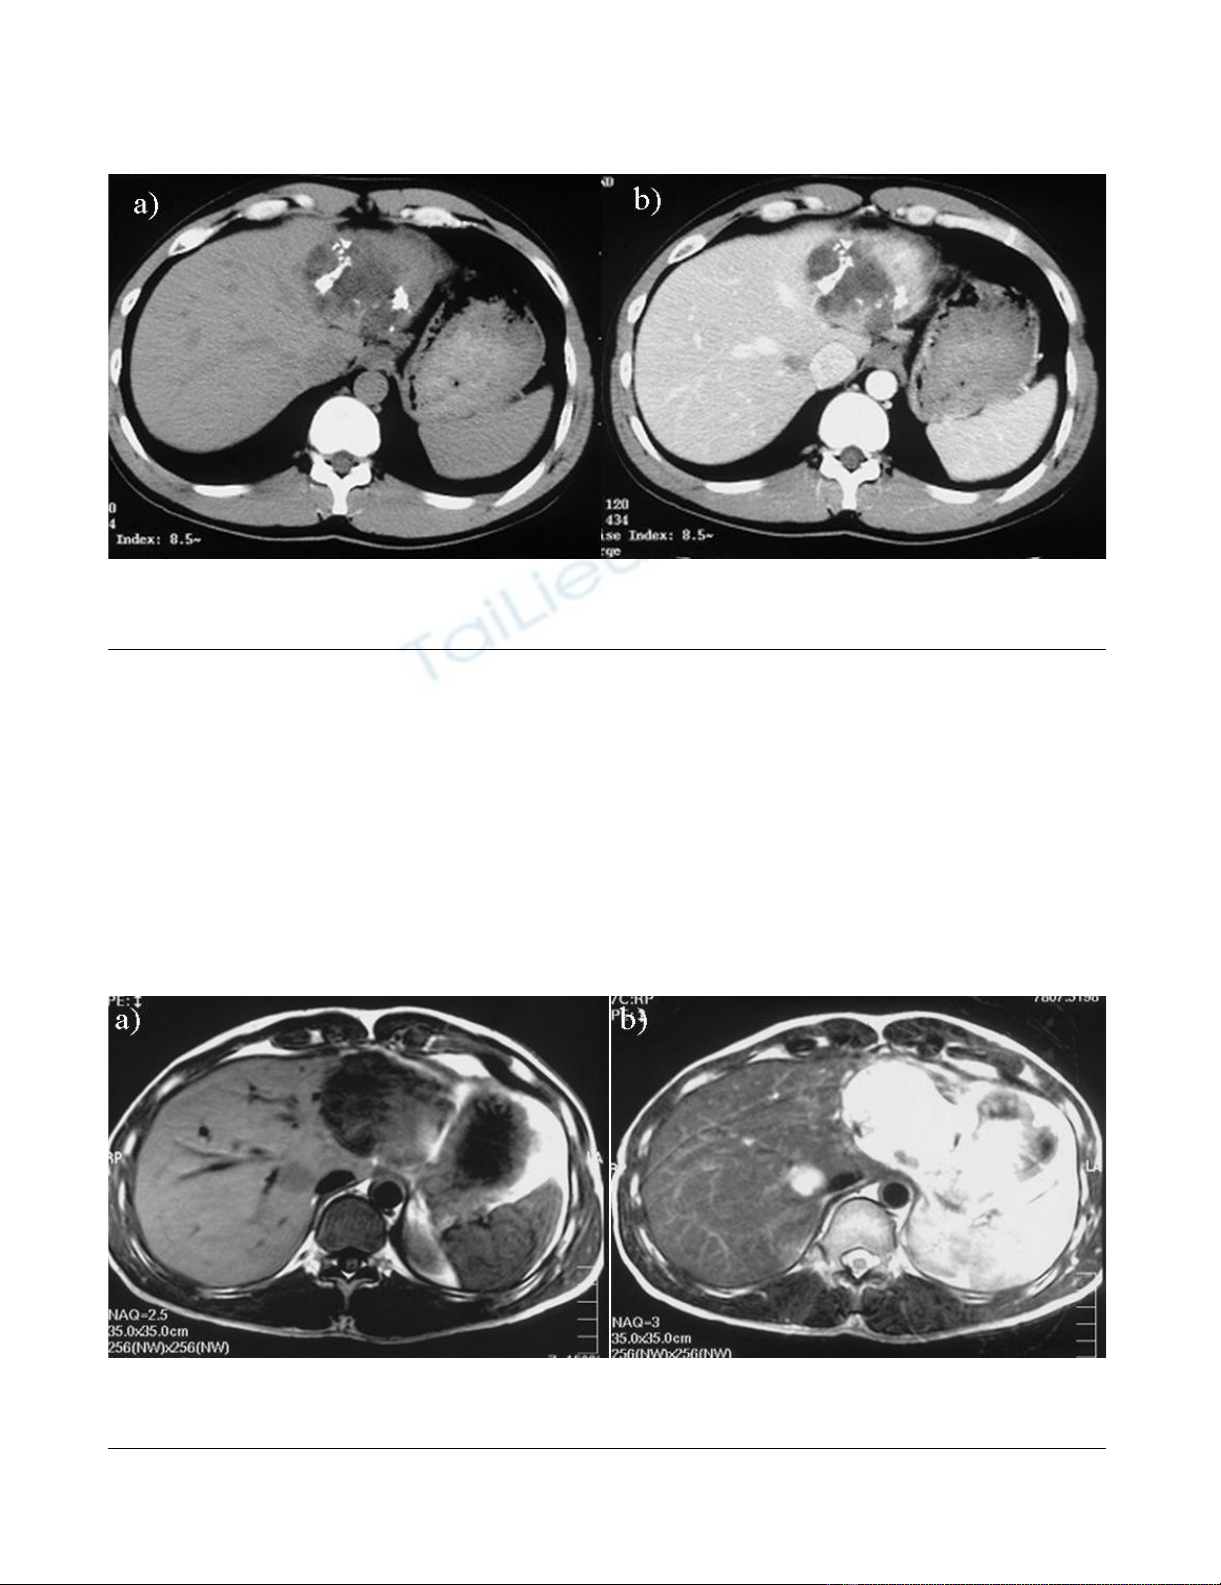

calcification and septa (Fig. 1b). An abdominal CT per-

formed on admission in 2004 showed that the unilocular

cyst had grown to over 10 cm in diameter with increasing

mounting calcification, septa and thickening of the wall

within the cyst (Fig. 2a, b). MRI revealed a partly low

intensity, partly high intensity T1-weighted image, and

high intensity T2-weighted image (Fig. 3a, b). US revealed

Abdominal CT findings in 2004Figure 2

Abdominal CT findings in 2004. a) showing the unilocular cyst over 10 cm in diameter, increasing eruplioid calcification,

septa and thickness of the wall within the cyst. b) the contrast was seen a little at the left side of the cyst.

Abdominal MRI in 2004, showing the unilocular cyst 10 cm in diameterFigure 3

Abdominal MRI in 2004, showing the unilocular cyst 10 cm in diameter. a) low intensity, partly high intensity on T1-

weighted image, b) high intensity on T2-weighted image were seen.